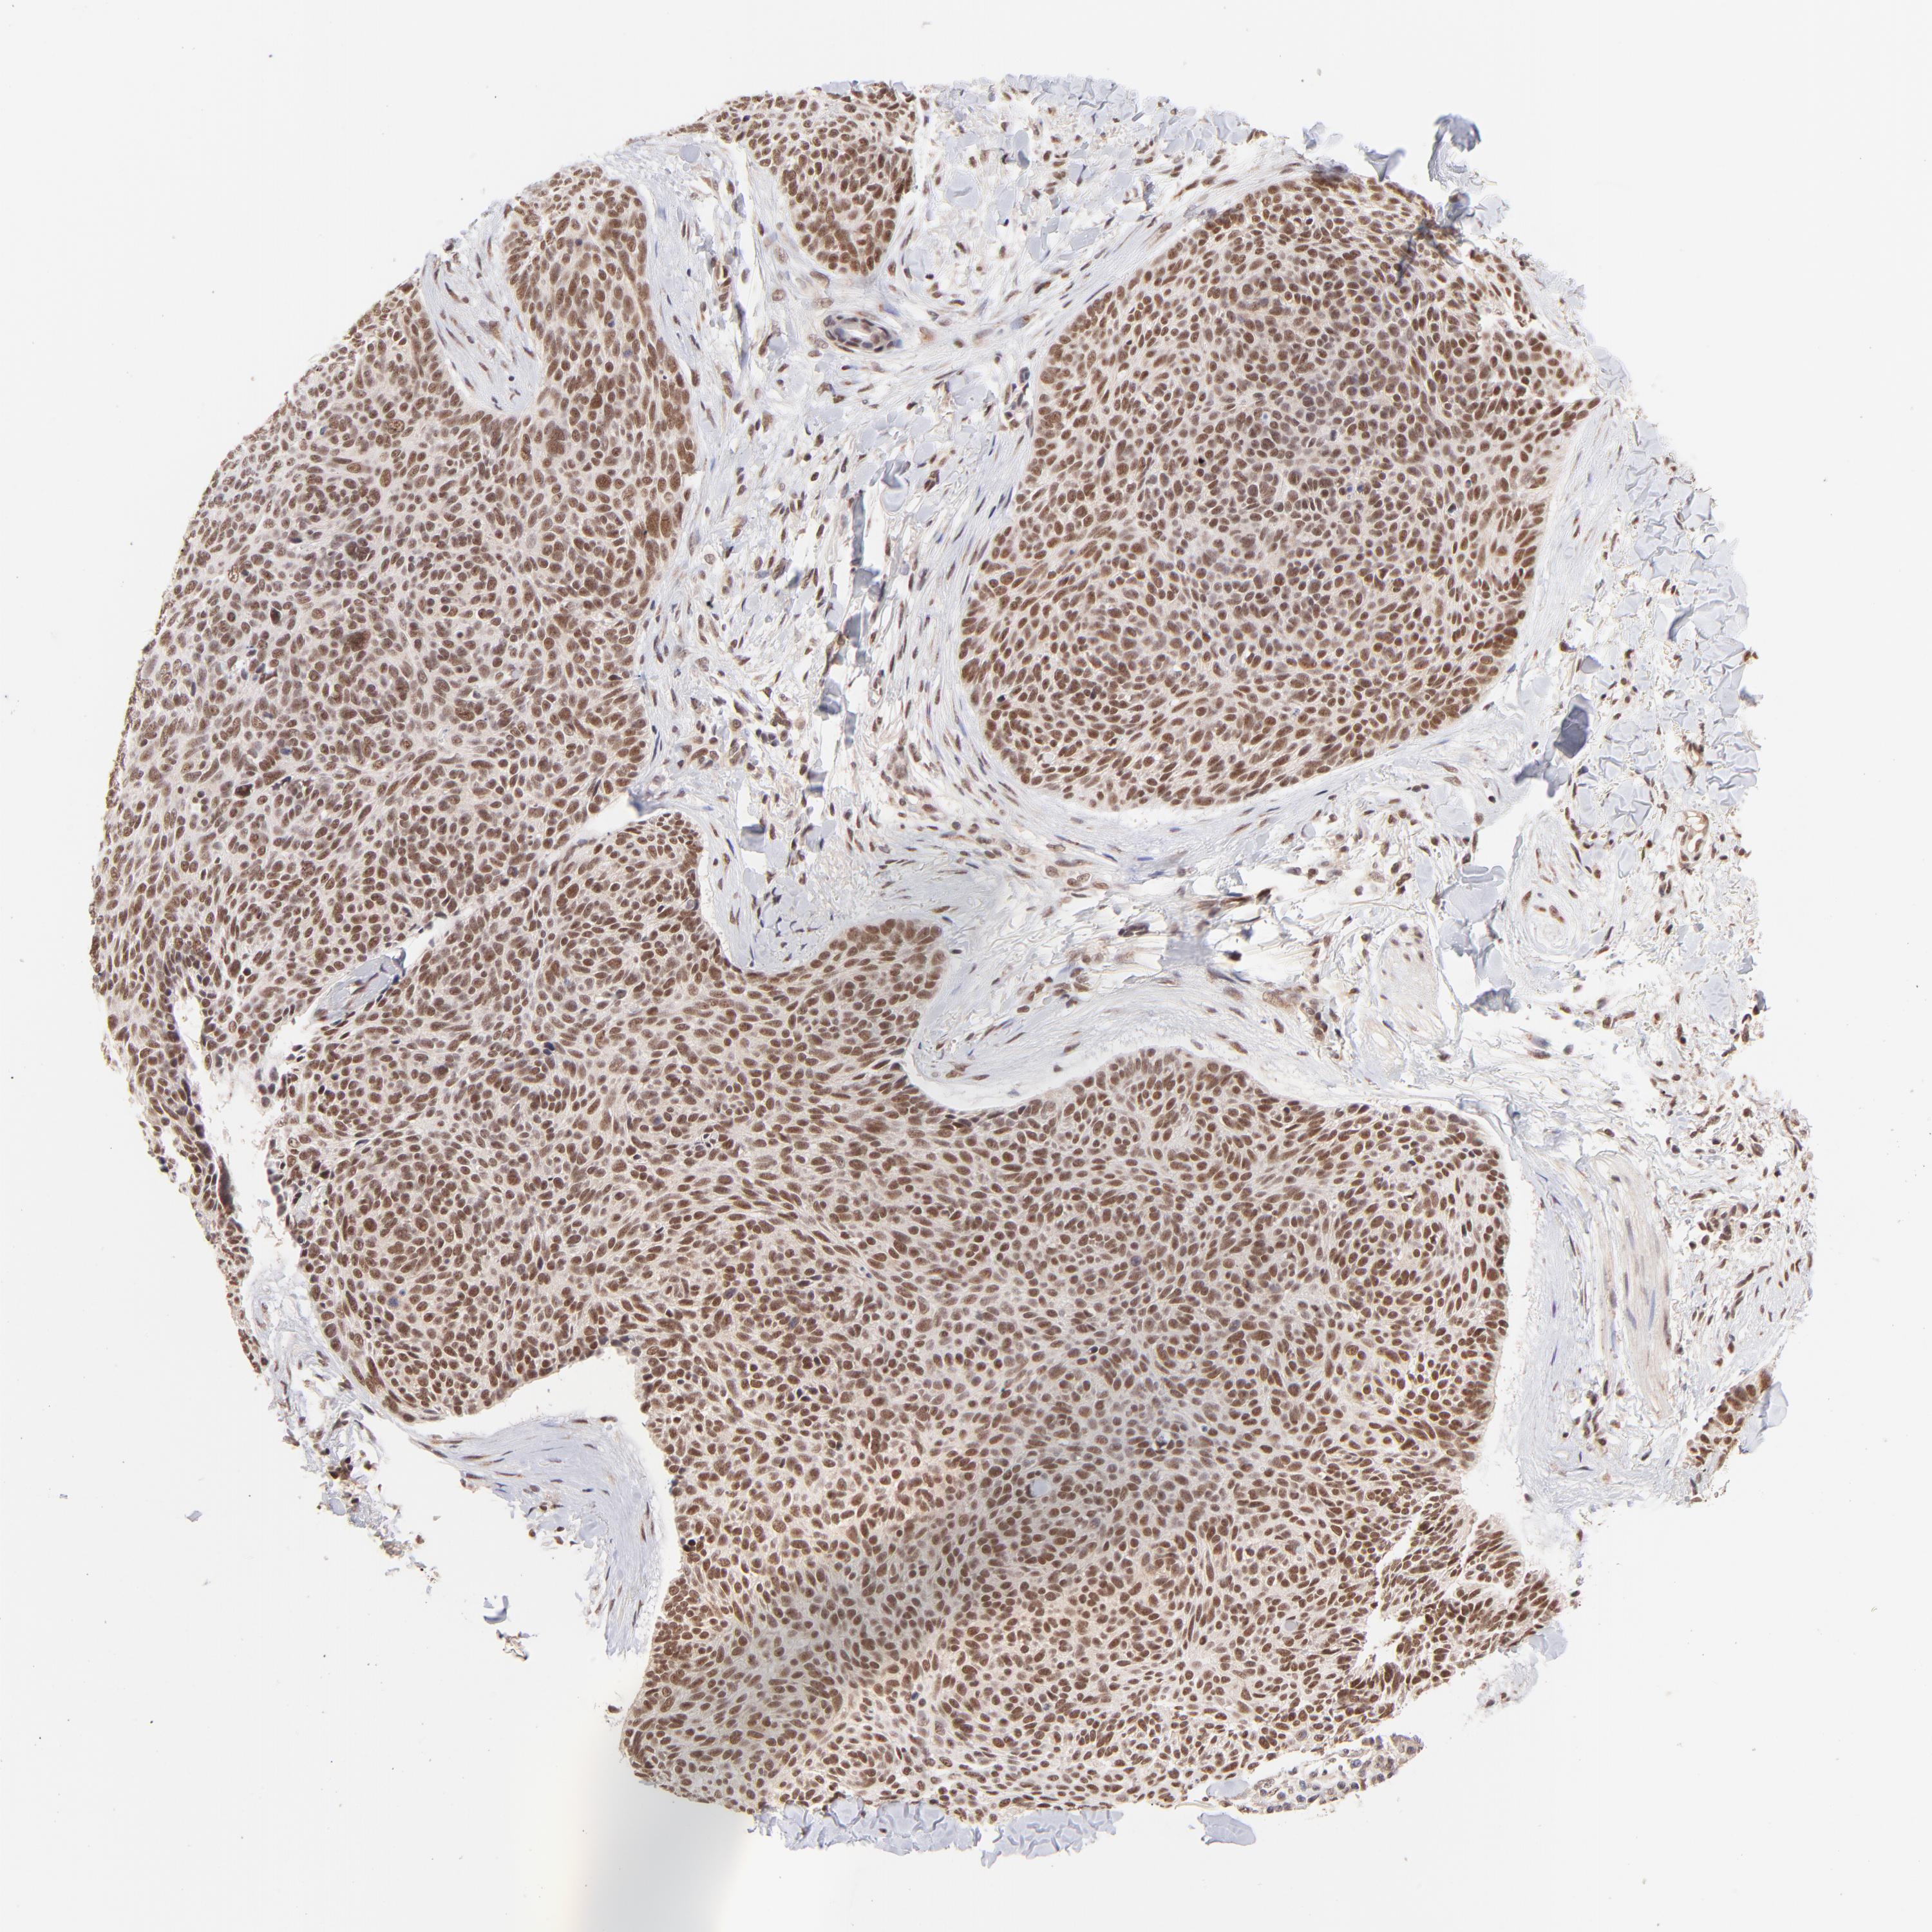

SKIN CANCER - Protein expressioni

A mouse-over function shows sample information and annotation data. Click on an image to view it in a full screen mode. Samples can be filtered based on level of antibody staining by selecting one or several of the following categories: high, medium, low and not detected. The assay and annotation is described here.

Antibody staining in the annotated cell types in the current human tissue is reported as not detected, low, medium, or high, based on conventional immunohistochemistry profiling in selected tissues. This score is based on the combination of the staining intensity and fraction of stained cells.

Each image is clickable and will lead to virtual microscopy that enables deeper exploration of all samples and also displays staining intensity scores, fraction scores and subcellular localization as well as patient and tissue information for each sample.

Antibody HPA003185

Staining

High

Intensity

Strong

Quantity

>75%

Location

Nuclear

Squamous cell carcinoma, NOS

Basal cell carcinoma